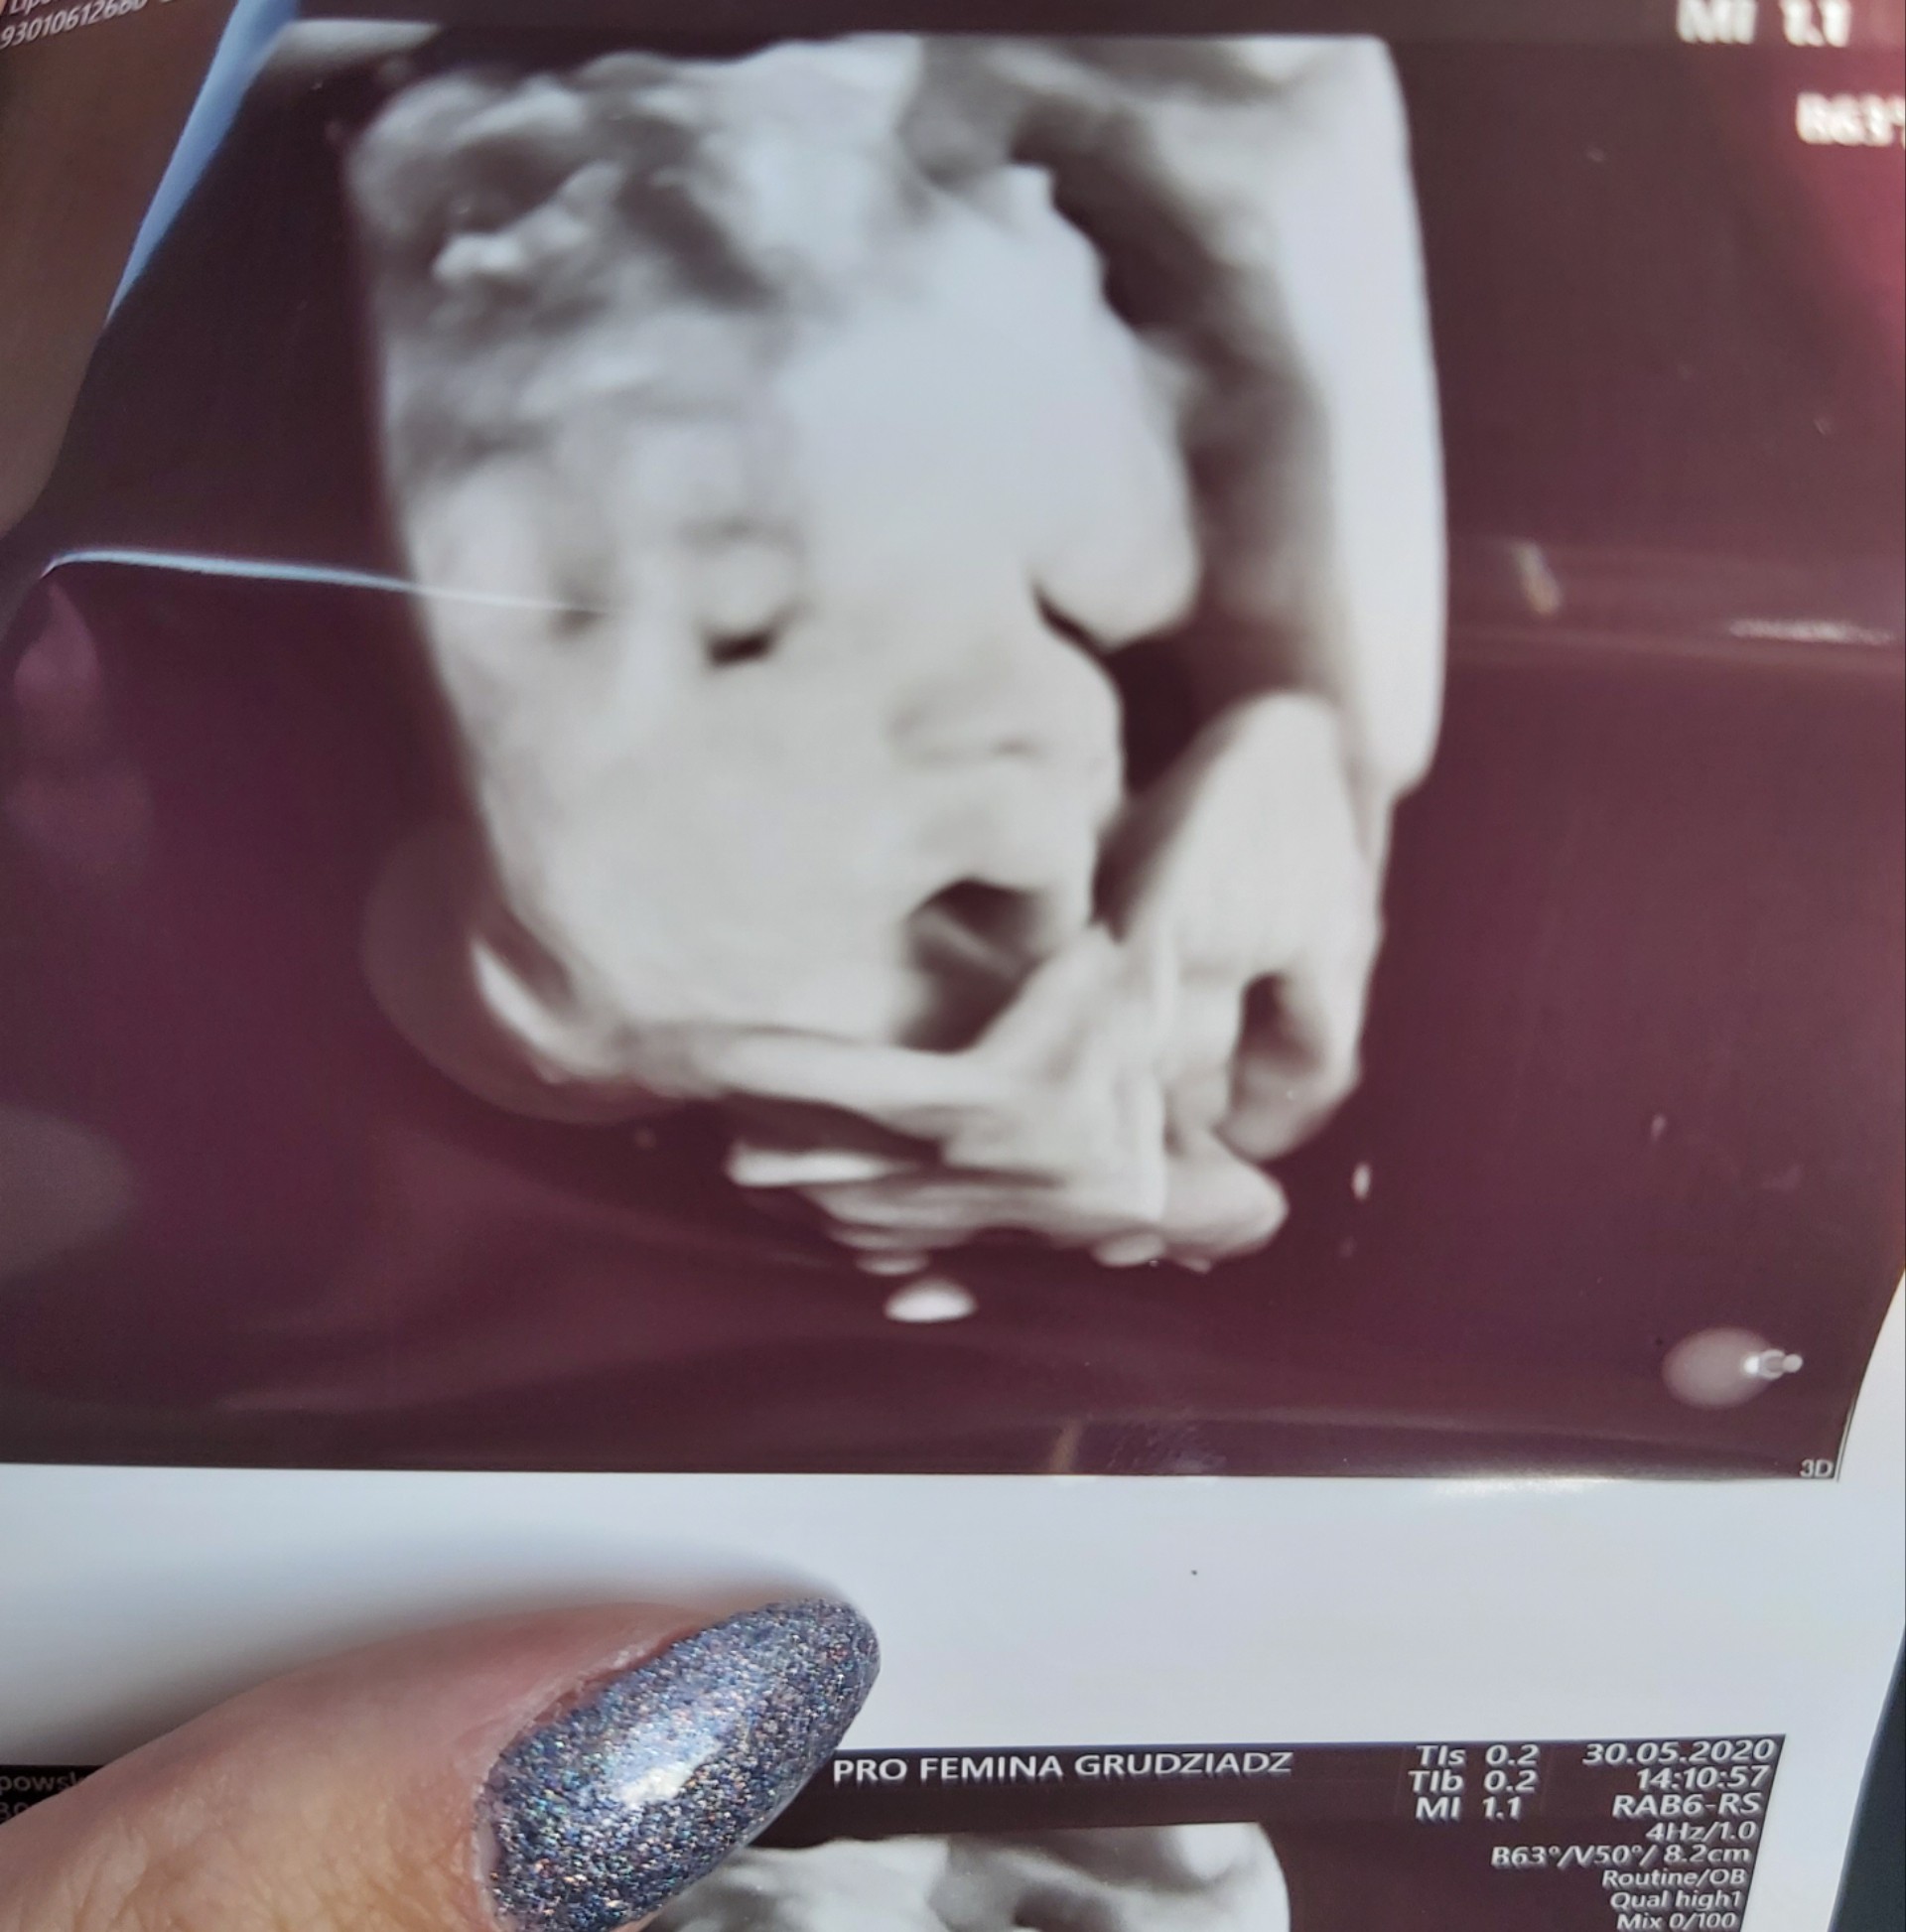

Patrycja piękne zdjęcia. I szczególne gratulacje